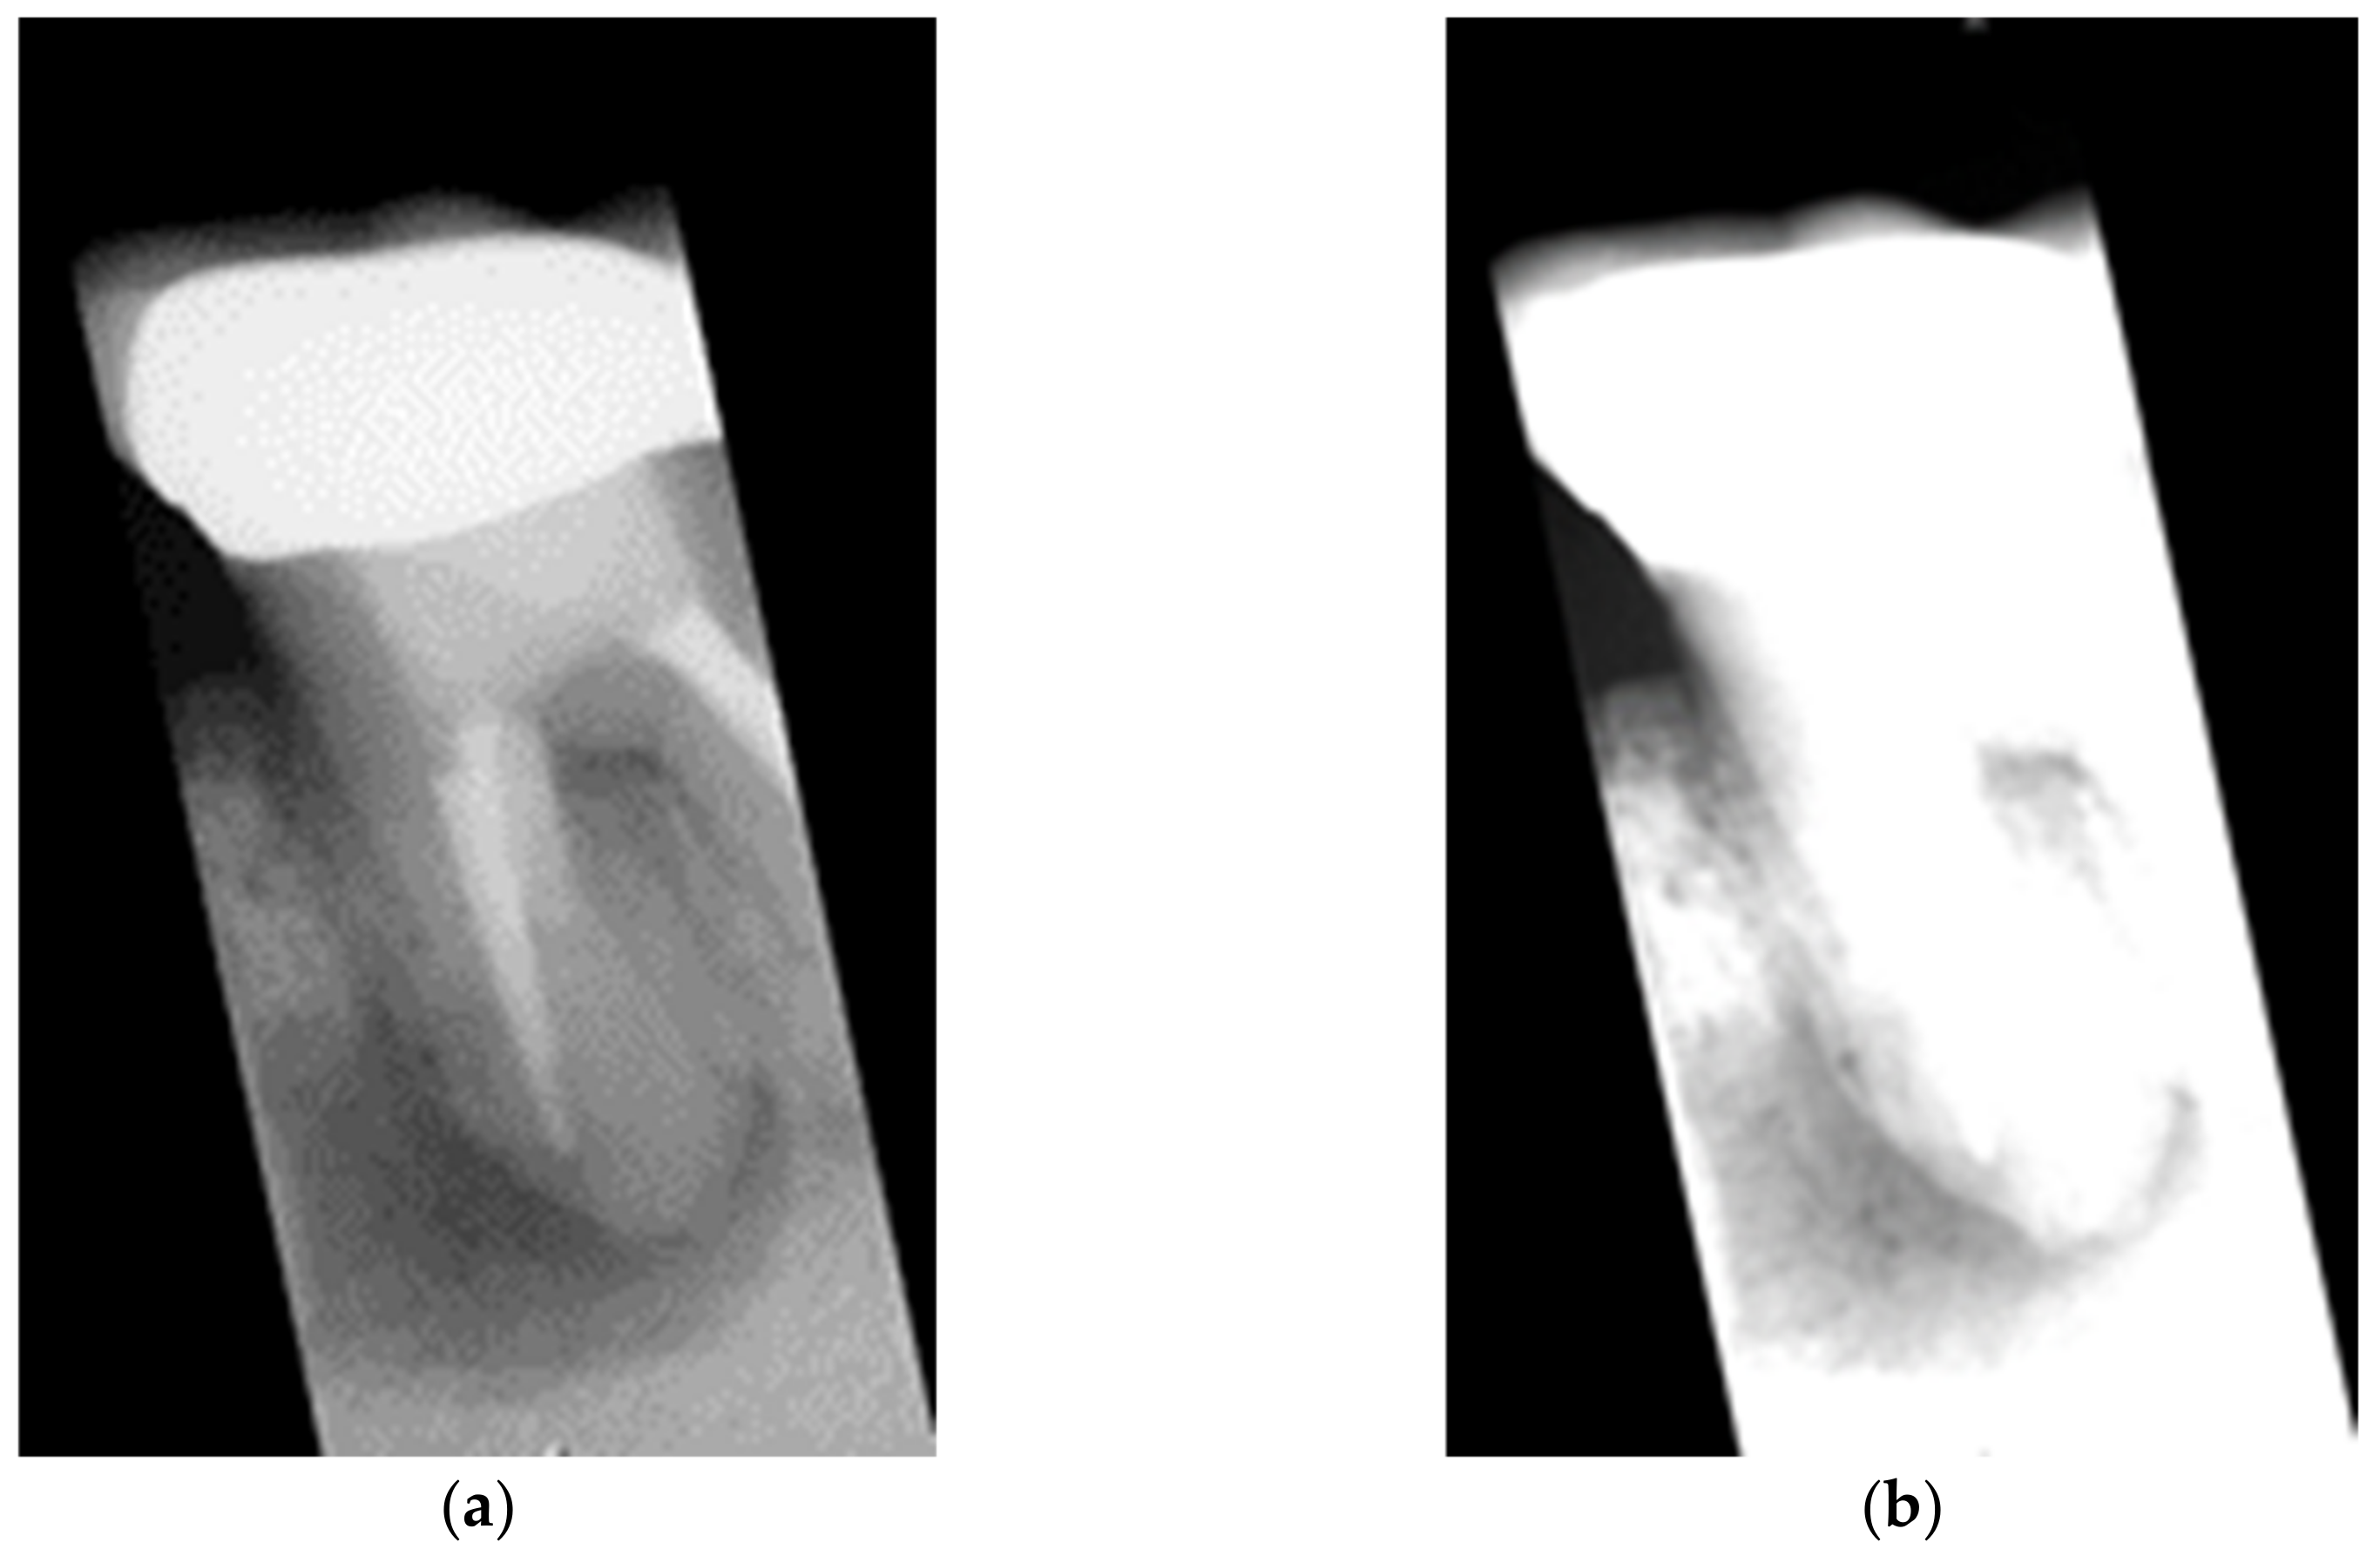

- In the image cropping preprocessing part, this study adds the adaptive threshold and angle rotation technology. Compared with the existing methods, this method significantly improves the image clarity and accuracy of a single tooth image.